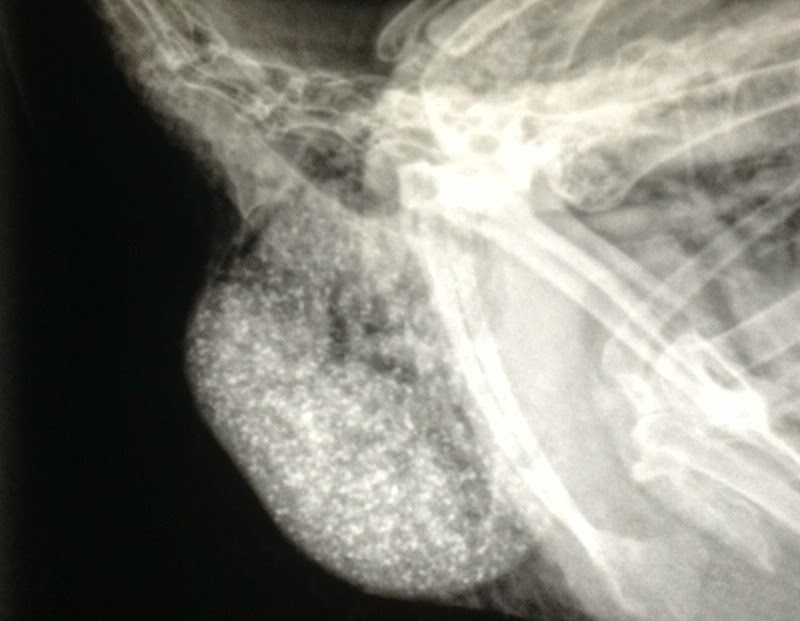

xray crop X-Ray: Impacted Crop by Bitchin' ChickensAugust 23, 2019 Comments 0 0 comments on “xray crop” Leave a comment Cancel reply Δ This site uses Akismet to reduce spam. Learn how your comment data is processed. Post navigation Previous Post